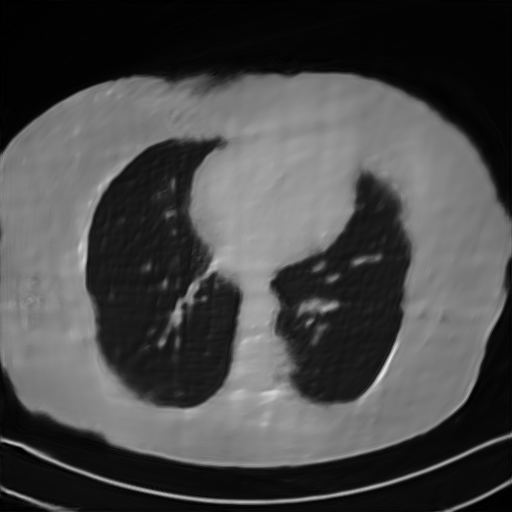

Fig. 4 presents the reconstruction results and residual images obtained by different methods for limited-angle reconstruction. As can be seen, the learning-based methods outperform the direct method and TV model, which exhibit serious artifacts in the missing angle region. Although the denoiser introduced by the FBP-Unet can somehow deal with the noises, the result still presents obvious artifacts. Compared to the SIPID, PD-net and FSR-nets, our LRIP-net1/2 can better preserve the image details and edges with less information left in the residual images. Thus, both the quantitative and qualitative results confirm that the low-to-high double-resolution strategy can improve the reconstruction accuracy for the limited-angle reconstruction problem.

We further increase the noise level contained in the raw data to 10% white Gaussian noises and list the quantitative results in Table IV. It can be observed that the reconstruction performance of the TV model is poor in the case of high-level noises with PSNR dropping by 4 to 5 dB compared to the previous experiments. On the other hand, the performance of the learning-based methods is less sensitive to noises. The SIPID method relying on the sinogram interpolation works better than FBP-Unet. And the deep unrolling methods (i.e., PD-net, IFSR-net, SFSR-net) outperform the traditional iterative algorithm when the scanning range is limited and data is corrupted by noises. Similar to the previous experiments, compared with other deep learning algorithms, our LRIP-nets give the reconstruction results with higher PSNR and SSIM. Moreover, the low-resolution image obtained by the projection data down-sampled with rate 1/8 always gives the best reconstruction results with more than 2 dB PSNR and 0.05 SSIM increments compared to the PD-net. Fig. 6 illustrates the reconstructed images from different methodologies with scanning angular range of and 10% Gaussian noises. It can be seen that the both TV model and the FBP-Unet suffers from significant artifacts, which present distortions in the angular range of the missing scan. Other learning-based methods provides better visual qualities than FBP-Unet, and our LRIP-net1/8 still gives the best reconstruction result with correct boundaries and fine structures.

Fig. 7 manifests the reconstruction results of these methods with scanning angular of . It can be seen that both FBP and FBP-Unet produce serious artifacts within the range of missing angles. The TV model performs well in removing Poisson noises, but it can not handle the artifacts very well. Similarly, there left obvious artifacts on boundaries and different degrees of missing in visceral tissues of the reconstruction images obtained by the SIPID, PD-net and FSR-net. The visceral tissue and boundaries of our LRIP-net reconstructions are more intact and smoother, especially for the LRIP-net1/8 which gives the ideal boundaries. The observation becomes even apparent if we look at the zoom-in regions, where the LRIP-nets can produce results with fine structures. Therefore, we conclude that the low-resolution image prior can effectively improve the qualities of the limited-angle CT reconstruction.